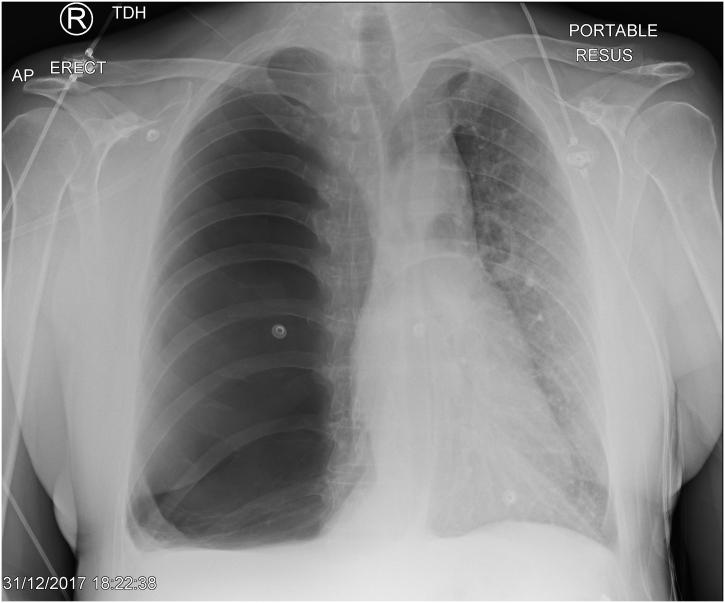

A 61 year old male with severe chronic obstructive lung disease presented to Accident and Emergency with progressive breathlessness. A chest radiograph showed a giant right sided bulla that was initially misinterpreted as a tension pneumothorax. Further review of his imaging and lung function pointed to him having vanishing lung syndrome. He was referred for a cardiothoracic opinion but was eventually managed conservatively.

Vanishing lung syndrome is characterised by a slowly enlarging upper lobe bulla that compresses normal lung parenchyma and causes mediastinal shift, with the patients experiencing increasing dyspnoea and reduced exercise tolerance. Smoking cessation is the mainstay of treatment. If they are relatively asymptomatic, patients are managed conservatively. Otherwise a variety of lung volume reduction techniques can be considered. A large bulla can look the same as a pneumothorax but the former does not have a lung edge and has a more rounded appearance. A CT scan is very useful in differentiating between the two pathologies. Bullae are predominantly caused by smoking. Bullae will cause high total lung volumes and residual volumes, but low alveolar volumes. Bullae can be observed or treated by surgical techniques.